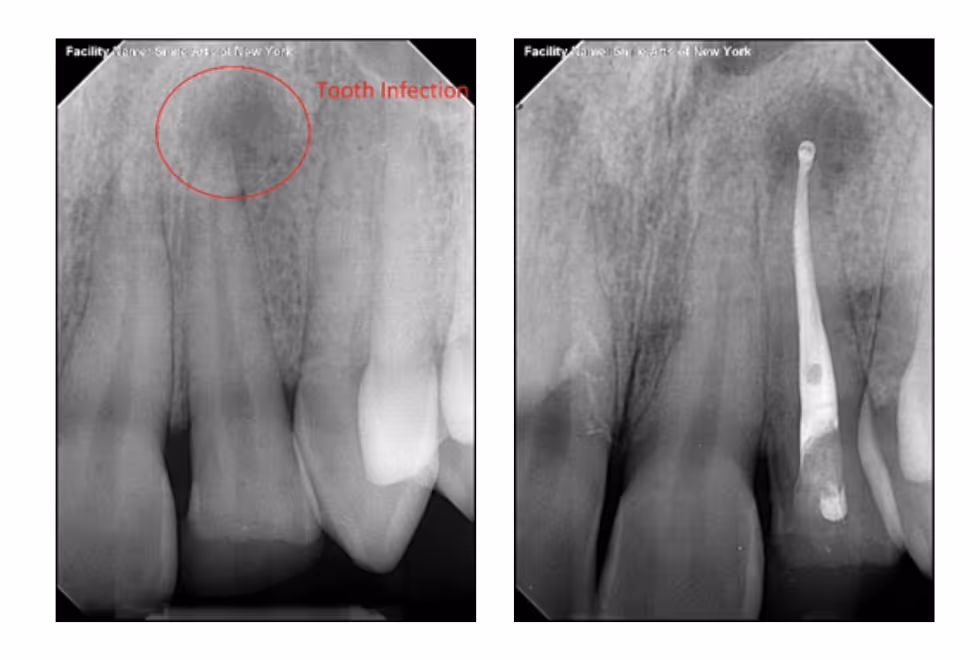

1. Diagnosis & X-ray

We begin with a detailed clinical exam and digital X-ray to assess the infected or inflamed pulp and surrounding bone.